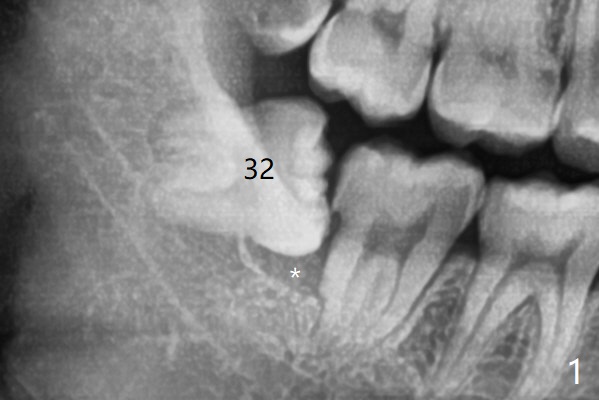

A 23-year-old man with poor oral hygiene presents to clinic with pain at #1 and 32.  Because of bone loss between #31 and 32 (Fig.1 *), Bond Apatite (1 cc, Fig.2 A) is placed in the defect area following insertion of Collagen Plug in the sockets (P, a half).  The other half of the Plug is placed coronal to Bond Apatite before suturing with 4-0 PGA.